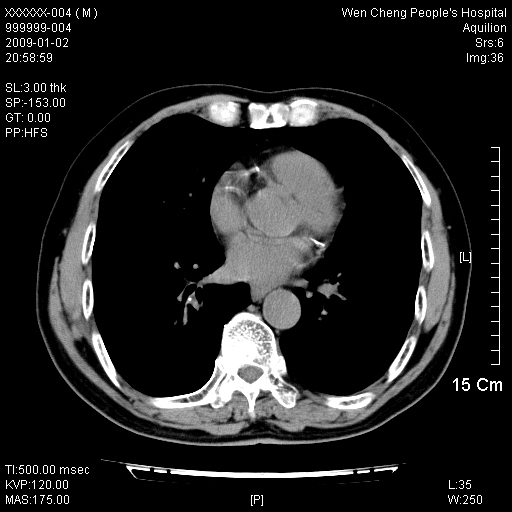

男性,73岁,有慢支病史,肿瘤系列标志物检验正常,血沉及血常规正常

右肺下叶背段小片状 磨玻璃样模糊影,内见血管及含气支气管像,支气管管壁增厚。考虑:慢性炎症!

1)不排除右肺下叶周围型肺癌可能;建议追踪复查。2)左右冠状动脉钙化。

右肺下叶背段小片状 实性与磨玻璃样影,内见血管及含气支气管像,支气管管壁增厚,边缘见长毛刺影。考虑:慢性炎症或肿瘤!建议抗炎治疗复查,密切观察随访!

右肺下叶片团状影内见扩张的含气支气管和支气管管壁增厚,其周有磨玻璃样模糊影和长毛刺。考虑慢性炎症可能性大。

2、右肺下叶片团状影内见扩张的含气支气管和支气管管壁增厚,其周有磨玻璃样模糊影和长毛刺。考虑周围型肺ca可能,结核不排。

高度提示细支气管肺泡癌,建议抗炎治疗半月观察病灶变化,如无明显改变,建议立即手术治疗.

病变形态非常不好呀,临床上血常规及症状也不明显,不太支持炎性病灶,高度警惕肿瘤病变,最好做个纤支镜检查。